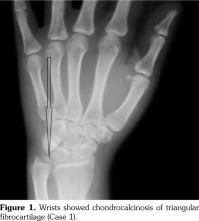

On examination, there was swelling and painful restriction of movement in her right knee. Imaging revealed calcification of cartilage of wrists, knee joints and hip joints although no microscopic confirmation was possible at this stage (Figure 1-4). She was investigated for a possible cause for CC, although investigations to screen for a metabolic cause turned out to be negative with a possibility for hereditary CC.